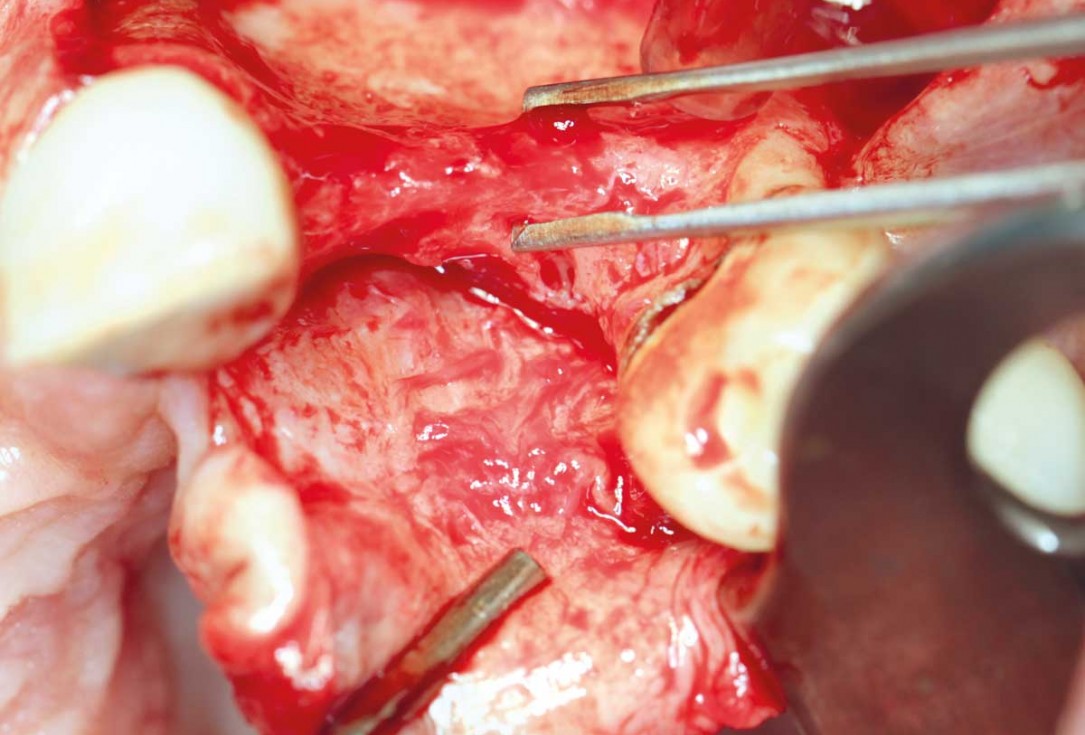

Preparation of a single tooth defect with severely resorbed vestibular wall